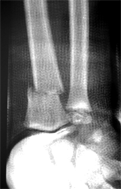

Les fractures de la métaphyse (partie basse de l'os) : |

Ce

sont les fractures les plus fréquentes de l'enfant : 20 à

36% selon les études. Elle touchent préferentiellement le côté non dominant : un droitier se fracturera plus le côté gauche. Le plus souvent elles font suite à une chute sur la main. Il

en existe plusieurs variétés en fonction de la forme de

la fracture, de la zone osseuse touchée : |

Ces fractures sont assez souvent faciles à diagnostiquer, en

raison du déplacement "en dos de fourchette".